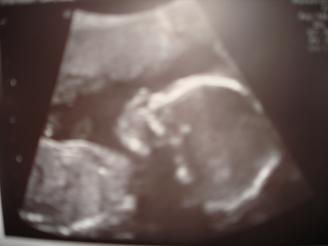

Re: Sono pics... can i see your 20 week ones?

My 20 week sono. Image Attachment(s):